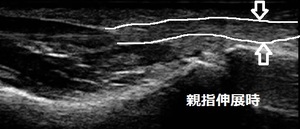

鶴ヶ島市 主婦 左母指の痛み、ばね指(弾発指、長母指屈筋腱の腱鞘炎)。

1週間前にボウリング練習後、ゴルフの練習に行きました。帰宅後、調理をしていると左手、親指が

曲がったままになっていることに気が付きました。無理に伸ばす時に「かっくん」と衝撃と痛みがあります。

超音波検査では親指を伸ばした状態から曲げたときに「かっくん」と衝撃があり、曲げた状態の時に

画像矢印の箇所(屈筋腱)が肥厚して腱がスムーズに滑走していない様子が認められました。

炎症で肥厚した腱を特殊な治療器で腱の腫れを取り除きます。早い方は数回の施術でひっかかり

が無くなって(時どきに引っかかっても痛みがほとんど無い状態になって)きます。